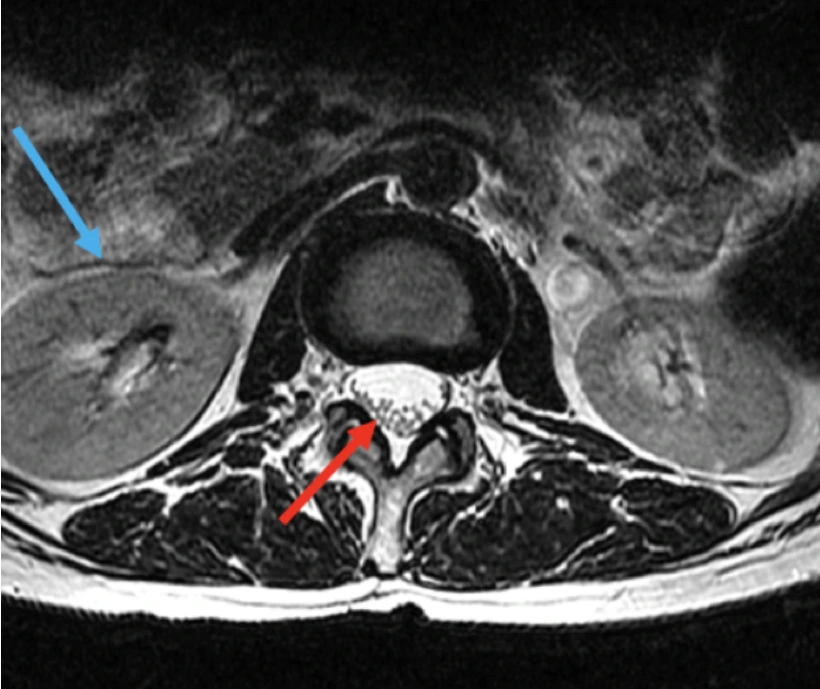

The technical quality of images varies widely from one device to another.

Slide the circle left or right to see how two scanners produce images of the same patient.

In the lower quality image, individual nerve roots and solid organ tissue are difficult to see

Nerve Roots

Organ Tissue

low resolution

high resolution